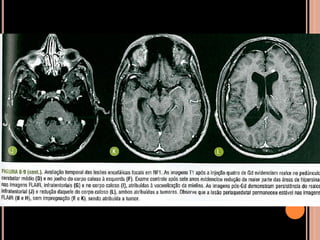

SÍNDROME DE STURGE-WEBER

 Angiomatose encéfalo trigeminal;

 Congênita rara; Considerada a princípio como

esporádica;

 Angiomatose venosa leptomeníngea, lesão

cutânea facial ispsilateral que coincide com o

território do trigêmio, envolvendo pelo menos sua

porção oftálmica; depósitos de cálcio cerebrais;

 Manifestações intracranianas: região de drenagem

venosa anormal e circulação colateral;

 Pode haver recrutamento de veias medulares para

drenagem do córtex (alteração angiomatosa de

plexo corioide aumenta dimensões e

vascularização);

 Circulação anormal  atrofia do parênquima

adjacente;

 Isquemia cerebral crônica –atrofia cortical

lentamente progressiva com calcificações

distróficas girais;

SSW

Recomendações

 RM com contraste (T1 ou FLAIR pós gadolínio);

 TC: calcificações girais (mas dispensável); não

aparecem antes dois 2 anos; Se suspeita procurar

os achados mais consistentes;